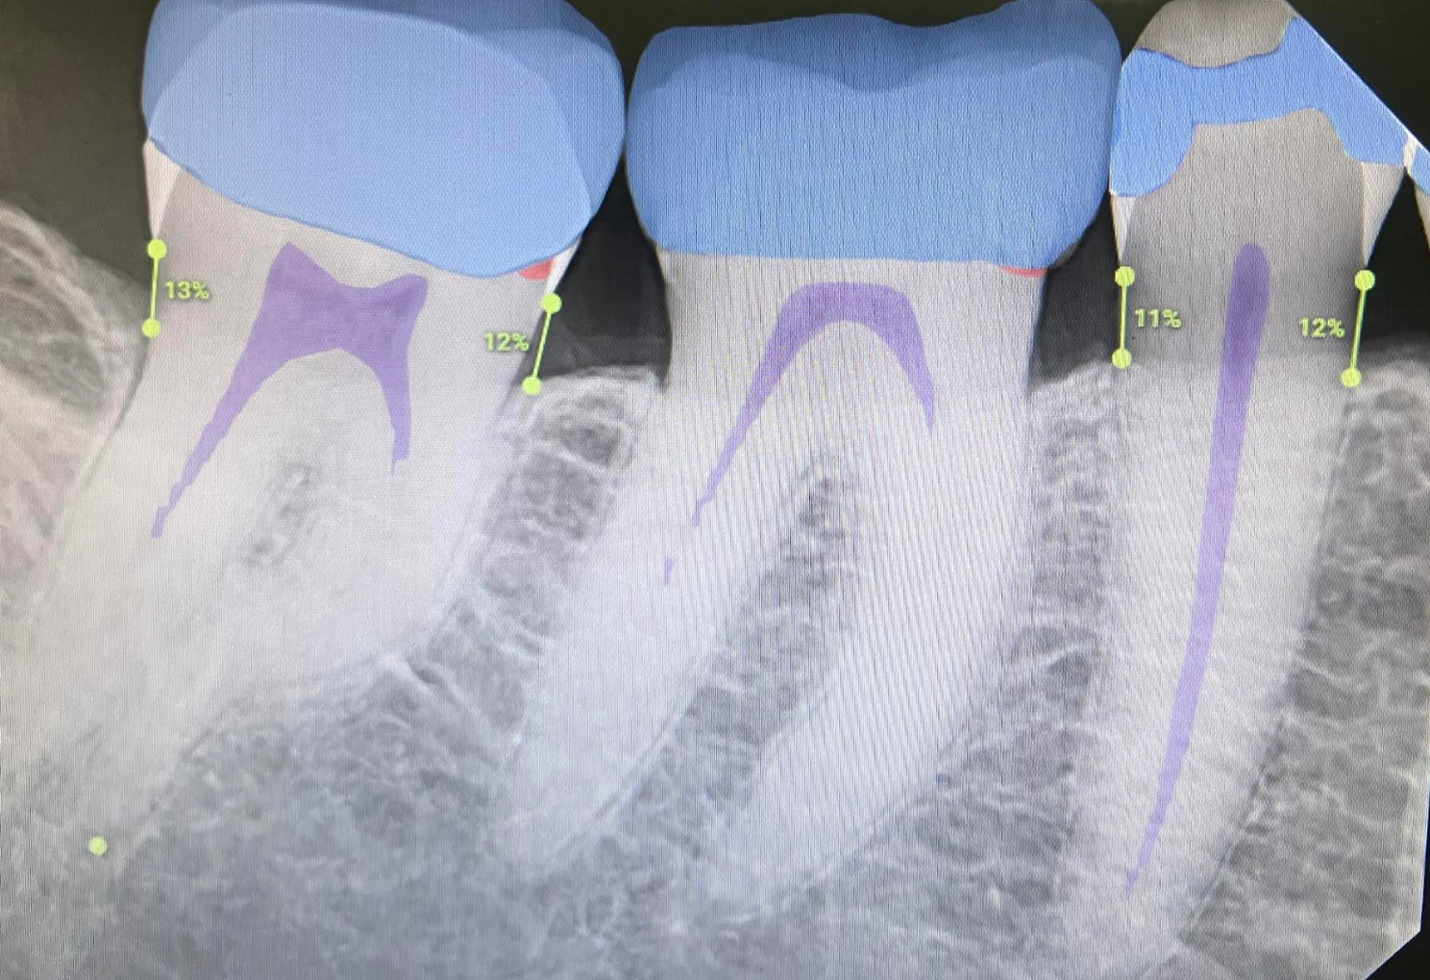

Example 2: Helping with training a hygienist

In this simple example we have a patient with restorative and periodontal needs. For a newer hygienist several things can be missed here that are made much more straightforward with Overjet:

Whereas a more inexperienced hygienist or associate might focus on the fact that the patient is missing a crown on tooth #21 and just mention that, with Overjet the full picture is seen:

And with the help of Overjet the patient has already had the discussion of the need for SRP, recurrent decay under crown #12, as well as the need for a crown on #21 ensuring simple dental work is not missed and also is easily shown to the patient. It is also listed for the hygienist to clearly see so they can start learning to identify subgingivial calculus, bone loss, and recurrent decay. It is also used against insurance company denial: